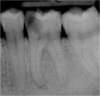

Exemple :

Une volumineuse carie s’est développée sur cette molaire inférieure. L’envahissement bactérien de la pulpe oblige le chirurgien-dentiste à nettoyer et désinfecter entièrement la cavité pulpaire (chambre pulpaire et canaux radiculaire), jusqu’aux extrémités des racines. Cet espace ainsi préparé est ensuite obturé de façon étanche (matériau blanc sur les radiographies).